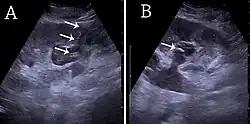

With US, larger stones (>5–7 mm) within the kidney, i.e., in the calyces, the pelvis and the pyeloureteric junction, can be differentiated, especially in the cases with accompanying hydronephrosis (Figure 18 and Figure 19). Hyperechoic stones are seen with accompanying posterior shadowing. Additional twinkling artifacts below the stone can often be seen using Doppler US. Large stones filling the entire collecting system are called coral stones or staghorn calculi and are easily visualized with US (Figure 20). Stones in the ureters are usually not visualized with US due to the air-filled intestines obscuring the insonation window. However, ureteral stones near the ostium can be visualized with a scan position over the bladder. An exam of the ureteric orifices and the excretion of urine to the bladder can be performed by inspecting the ureteric jets in the bladder with color Doppler US.

Figure 19. Centrally located stone with posterior shadowing. No hydronephrosis is present. Measurement of kidney length on the US image is illustrated by '+' and a dashed line.[1] -

Figure 20. Staghorn calculi filling the entire collecting system and creating pronounced shadowing.[1] -